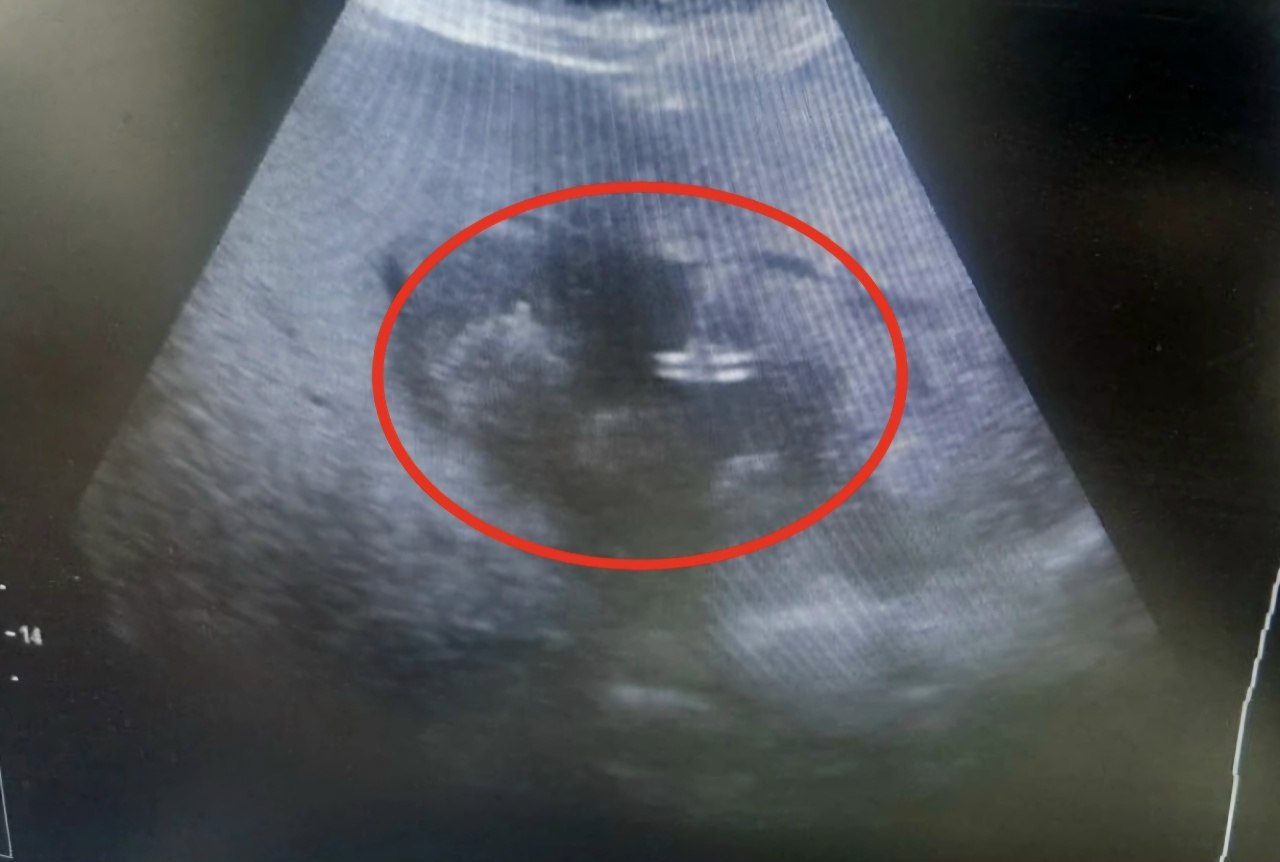

В гнойное хирургическое отделение Балаковской больницы поступила 83-летняя пациентка. У нее диагностировали обширный абсцесс печени размером около 10 см.

Учитывая возраст пациентки, традиционное полостное оперативное вмешательство было очень опасно. Тогда врачи приняли решение выполнить малоинвазивное дренирование абсцесса печени. Эта методика позволяет с ювелирной точностью ввести дренаж в полость гнойника и минимизировать травмы тканей.

Наша задача — обеспечить безупречную навигацию для хирургов, чтобы дренаж попал строго в целевую зону, исключив повреждение окружающих тканей. Это дает возможность пожилым пациентам восстанавливаться быстро, — рассказала заведующая отделением ультразвуковой диагностики Ирина Власова.